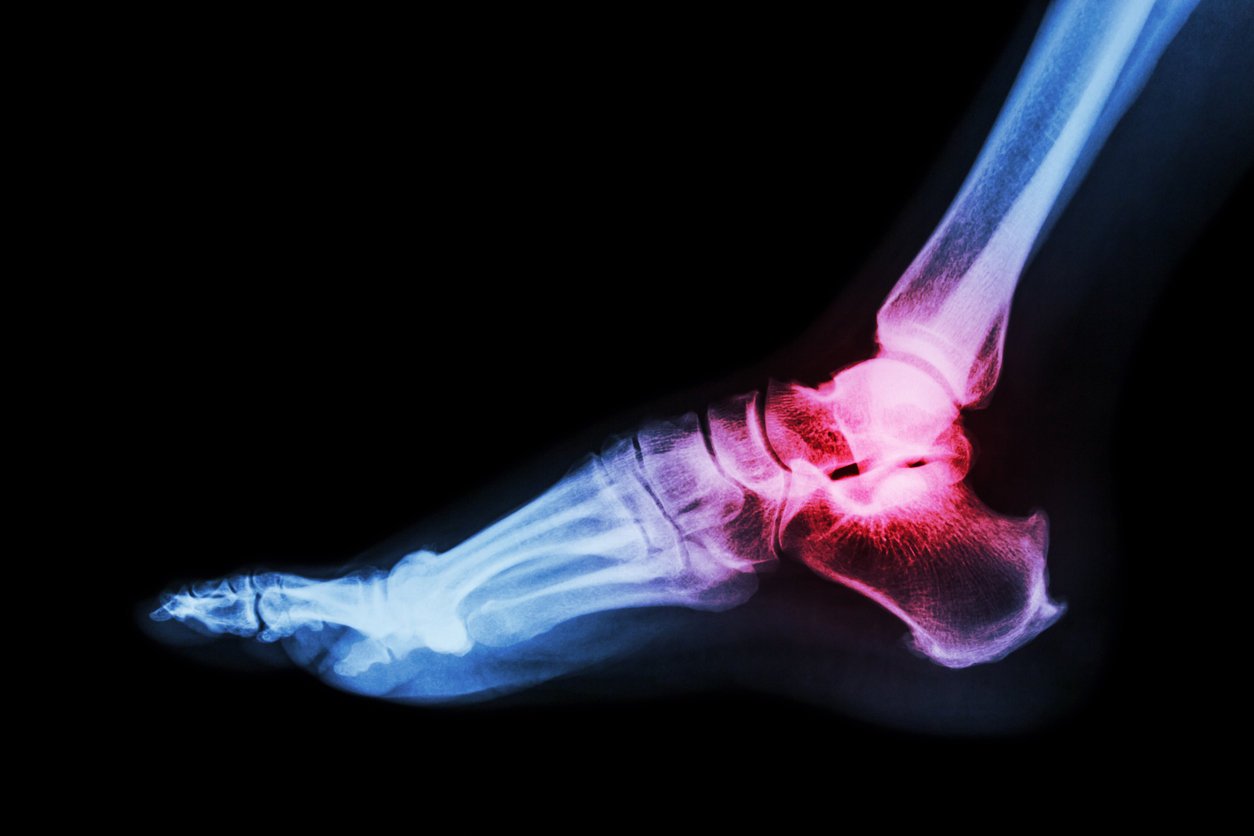

arthritis at ankle joint (gout , rheumatoid arthritis)

Istock

Cette maladie conduit à la destruction du cartilage et s’étend à toutes les structures de l'articulation. À titre de précision, le cartilage tapisse les extrémités osseuses d’une articulation, leur permettant de glisser l’une sur l’autre. "Dans l’arthrose, il perd en épaisseur, se fissure et finit par disparaître. Cela entraîne des douleurs et un handicap majeur avec une perte de mobilité", partage de son côté l’Inserm. Le diagnostic passe par une radio.